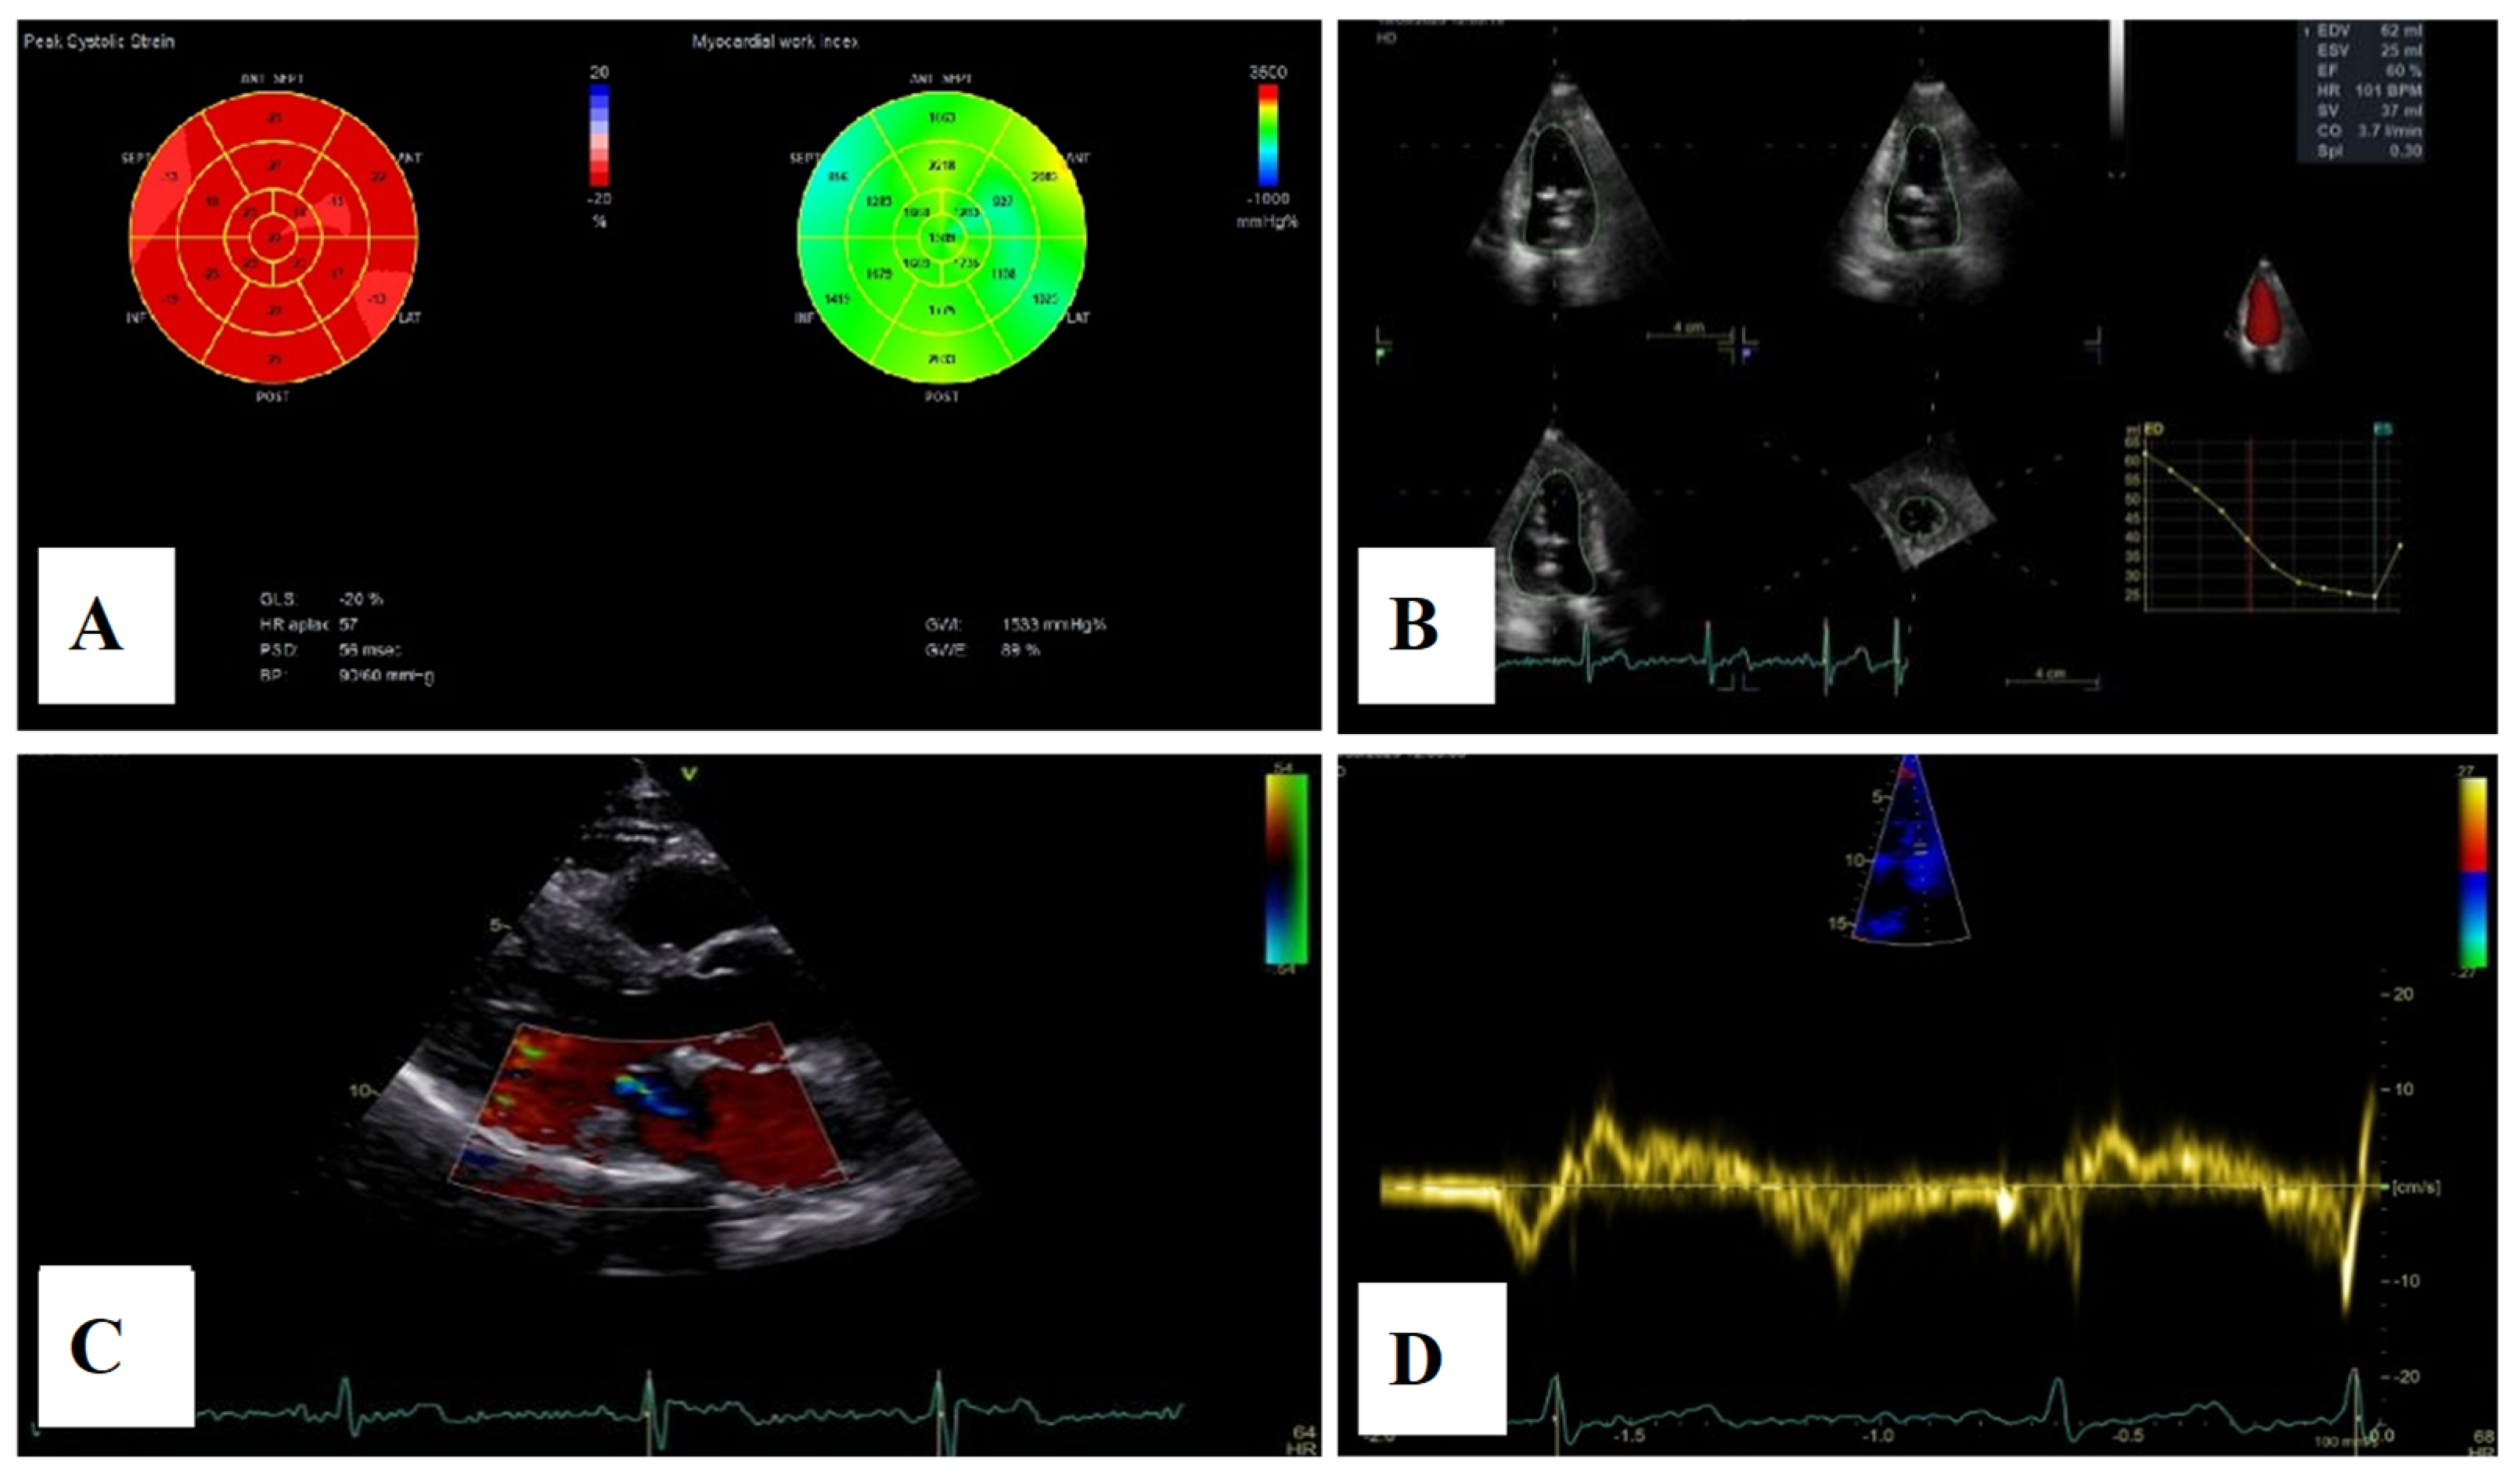

Severe mitral regurgitation was identified, manifested by an eccentric regurgitant jet and associated left atrial dilatation (Figure 4). Moderate tricuspid regurgitation with right atrial dilatation was also present. Both the left and right ventricles were of normal size and function. Global longitudinal strain was preserved for both ventricles, with an average of −22.9% for the left ventricle and −22.0% for the right ventricle, although a mild degree of dispersion in longitudinal strain peaks was observed (Figure 5).

Figure 5.

2D speckle-tracking echocardiography used as a tool for assessing left ventricular systolic performance (GLS average −22.9%), with some degree of dispersion in longitudinal strain peaks.

Echocardiographic assessment demonstrated a reduction in left atrial and ventricular volumes, as measured by three-dimensional volumetry, with improvement in left atrial contractile function. Mitral regurgitation remained mild, and no recurrence of mitral annular disjunction was noted (Figure 11). Tricuspid regurgitation remained mild throughout the follow-up period, with a slight reduction in right atrial and ventricular dimensions and preserved right ventricular function.

Figure 11.

(A)—2D speckle-tracking echocardiography, displaying normal global longitudinal strain (−20%) and myocardial work bull’s-eye plot, displaying normal range of GWI (global work index—1533 mmHg%). (B)—Left ventricular volumetry and systolic function assessed by 3D echocardiography, showing normal volumes and ejection fraction—EF–60%. (C)—The parasternal long-axis view displays trivial mitral regurgitation without mitral annular disjunction. (D)—Tissue Doppler imaging on the lateral mitral annulus, without Pickelhaube sign.